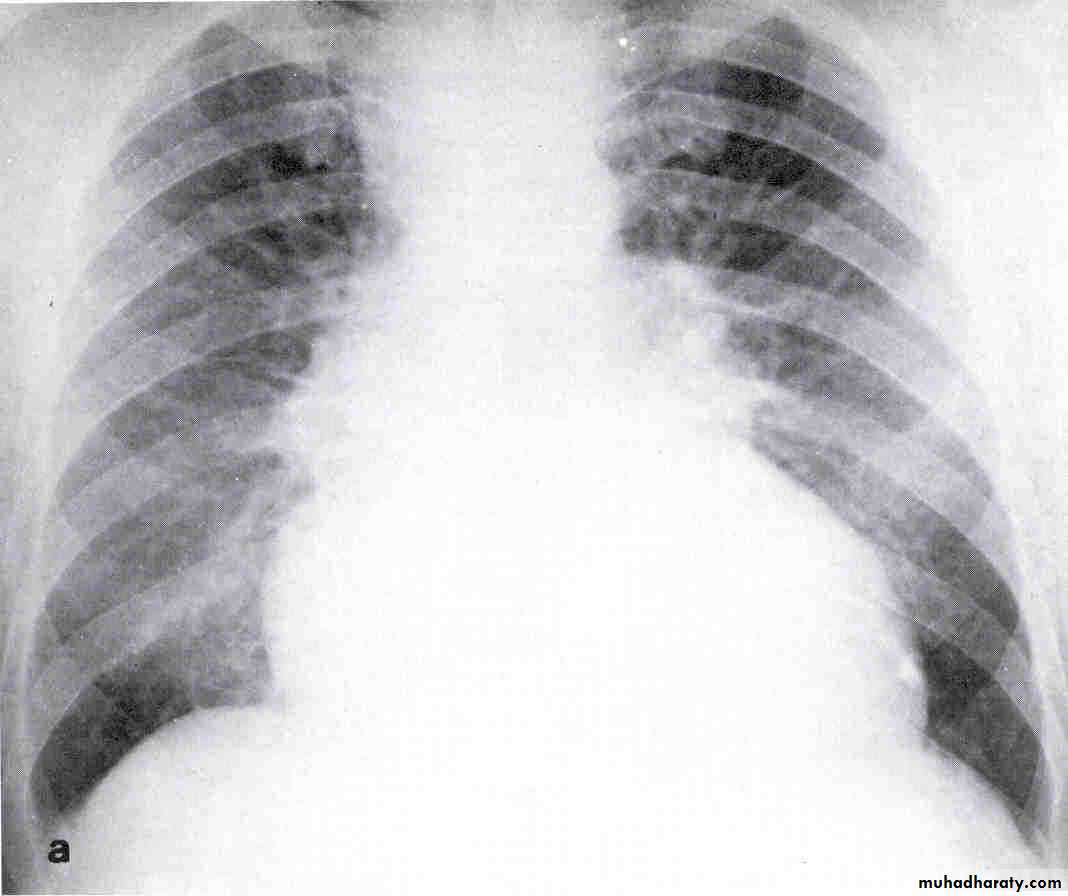

Chest X-ray

Look for Heart sizePulmonary vascular markings

COPD, pneumonia, Pneumothorax, widened mediastinum

Pleural effusions

Chest X- ray